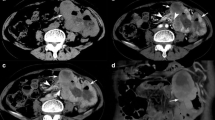

The presence of EUS- and CT-based morphological high-risk features, including calcification, necrosis, intratumoral heterogeneity, irregular border, or surface ulceration, did not differ between very-low and intermediate risk 1–2-cm gGISTs (p > 0.05). The radiomics model consisting of five radiomics features showed favorable performance in discrimination of malignant 1–2-cm gGISTs, with the AUC of the training, validation, and testing cohort as 0.866, 0.812, and 0.766, respectively.

Instead of CT- and EUS-based morphological high-risk features, the CT radiomics model could potentially be applied for preoperative risk stratification of 1–2-cm gGISTs.